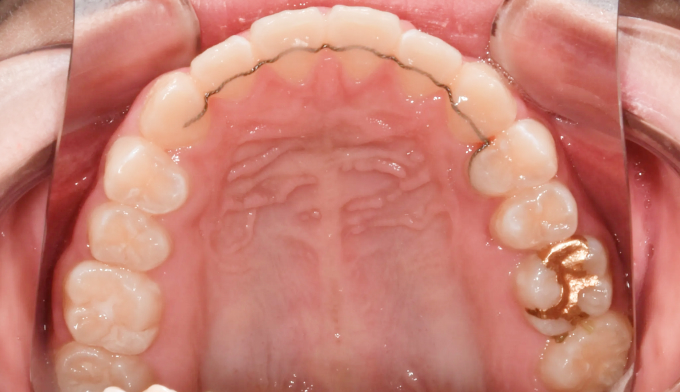

본 케이스처럼 아예 치아의 각도가 누워버린 경우에는 억지로 교정장치를 부착하여 치아를 제 위치로 당겨주어야 합니다.

잇몸의 일부를 절개하여 교정장치 부착후 치아를 견인하였고 총 치료기간은 16개월입니다.